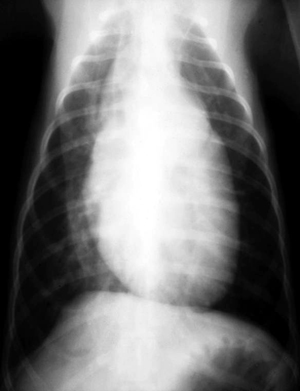

Wie sieht ein Röntgenbild von einem Tier mit PDA aus?

Röntgenbild:

Die Röntgenbefunde sind abhängig von der Größe des Defektes. Bei kleinen Defekten ist das Röntgenbild unauffällig oder nur leicht verändert. Bei größeren Defekten vergrößert sich das Herz und man sieht die Zeichen der vermehrten Lungendurchblutung. Auffällig sind in den meisten Fällen von PDA's bei Hunden eine deutliche Kardiomegalie.